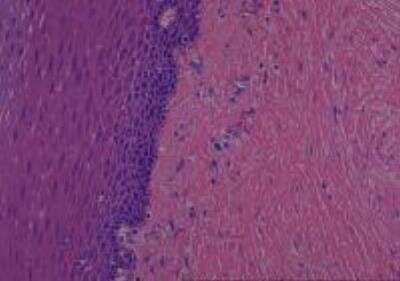

Scientific Data Images for Human Multi Tissue MicroArray (Normal Adjacent)